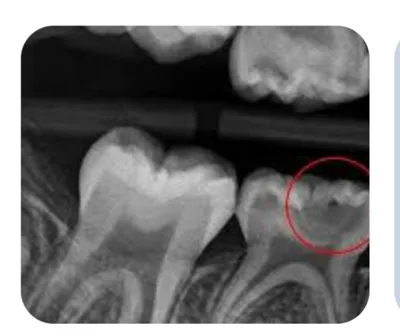

برسی دقیق عکس دندان شما